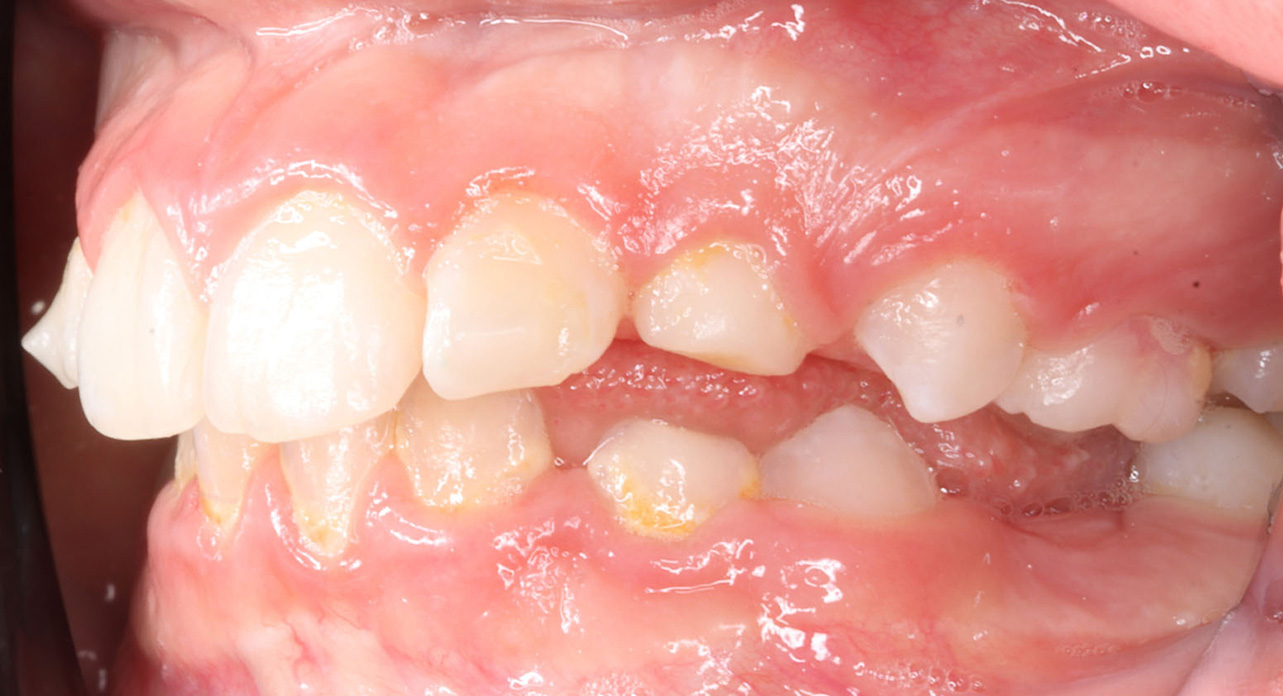

Case report of a 9-year-old female patient in the intermediate phase of mixed dentition. The patient presents with moderate upper and lower crowding, narrow arches, Class II molar relationship on the right side, premature loss of tooth 83, deviation of the lower midline to the right, deep bite, and a crossbite on the right side affecting only the deciduous dentition.

Class II elastics were programmed, using hooks on the upper deciduous canines and Integrated hooks (IH) on the lower molars. The elastics were prescribed for 24-hour daily use, with a force of 3/16″ 4 oz. A virtual Class II elastic jump was requested from the technician.